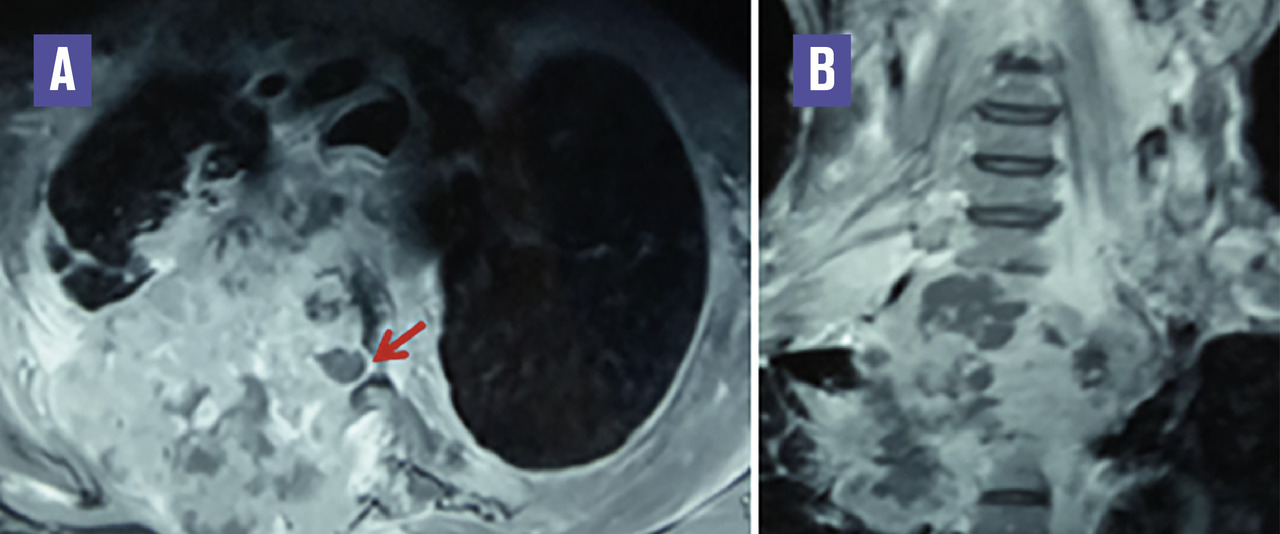

Cet homme de 52 ans, fumeur non sevré, consultait pour une douleur dorsale supérieure droite depuis 3 mois et un déficit moteur des 4 membres d’installation progressive. L’examen clinique notait une tétraparésie spastique et une dyspnée de stade IV. La tomodensitométrie (TDM) thoracique (fig. 1 ) montrait un processus tumoral de l’apex pulmonaire droit envahissant les deux premières côtes homolatérales ainsi que les deux premières vertèbres dorsales. Le diagnostic de la tumeur de Pancoast-Tobias était retenu. Une imagerie par résonance magnétique (IRM) médullaire était réalisée, montrant l’extension tumorale endocanalaire et la compression de la moelle épinière (fig. 2 ).

La tumeur de Pancoast-Tobias se situe à l’apex pulmonaire, infiltre par contiguïté les tissus de la paroi thoracique apicale (côtes, vertèbres) et peut envahir l’orifice thoracique supérieur.1 Elle cause douleur thoracique, névralgies cervicobrachiales, syndrome de Claude-Bernard-Horner et atrophie musculaire du membre supérieur ; avec parfois un œdème du membre supérieur (par thrombose de la veine sous-clavière), et des signes de compression médullaire (par extension tumorale endocanalaire).1 La TDM fait le diagnostic, analyse les rapports de la tumeur avec les structures adjacentes, détecte une thrombose veineuse (notamment de la sous-clavière), et analyse l’extension tumorale locorégionale et à distance. L’IRM cherche une souffrance médullaire et analyse l’orifice thoracique supérieur. Le diagnostic histologique conditionne la décision thérapeutique. Il s’agit fréquemment d’un carcinome de stade T3 ou T4 de la classification TNM.1, 2 Une chimio-radiothérapie néoadjuvante suivie d’une résection tumorale complète, même en cas d’envahissement vertébral, permet un pronostic de plus en plus proche de celui d’un cancer pulmonaire non apical de stades similaires.2